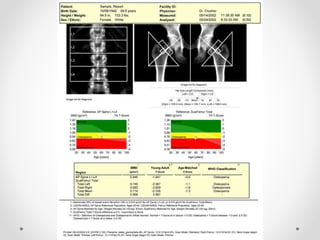

DEXA

(dual-energy x-ray absorptiometry)

• Measures x-ray absorbed by calcium in bone

• Reflects density

• Gold standard

T-scores vs. Z-scores

 T-score: calculated by comparing current BMD to the

mean peak BMD of normal young adult of same gender

(white)

 applied to postmenopausal women

 Z-score: based on difference between the individual’s

BMD and mean of a reference population of same

gender, age, ethnicity

 Used for premenopausal women under age 50

World Health Organization

Classification

Classification Bone Mineral Density Criteria

Normal Above -1.0 SD of young adult peak

mean value

Osteopenia (Low Bone Mass) Between -1.0 SD and -2.5 SD of young

adult peak mean value

Osteoporosis Below -2.5 SD of young adult peak

Note that these are standard deviations from young adult

peak bone mass (T-score)

This classification applied to DEXA measurements only;

cannot be compared to other modalities

Classification is based on the lowest measured score